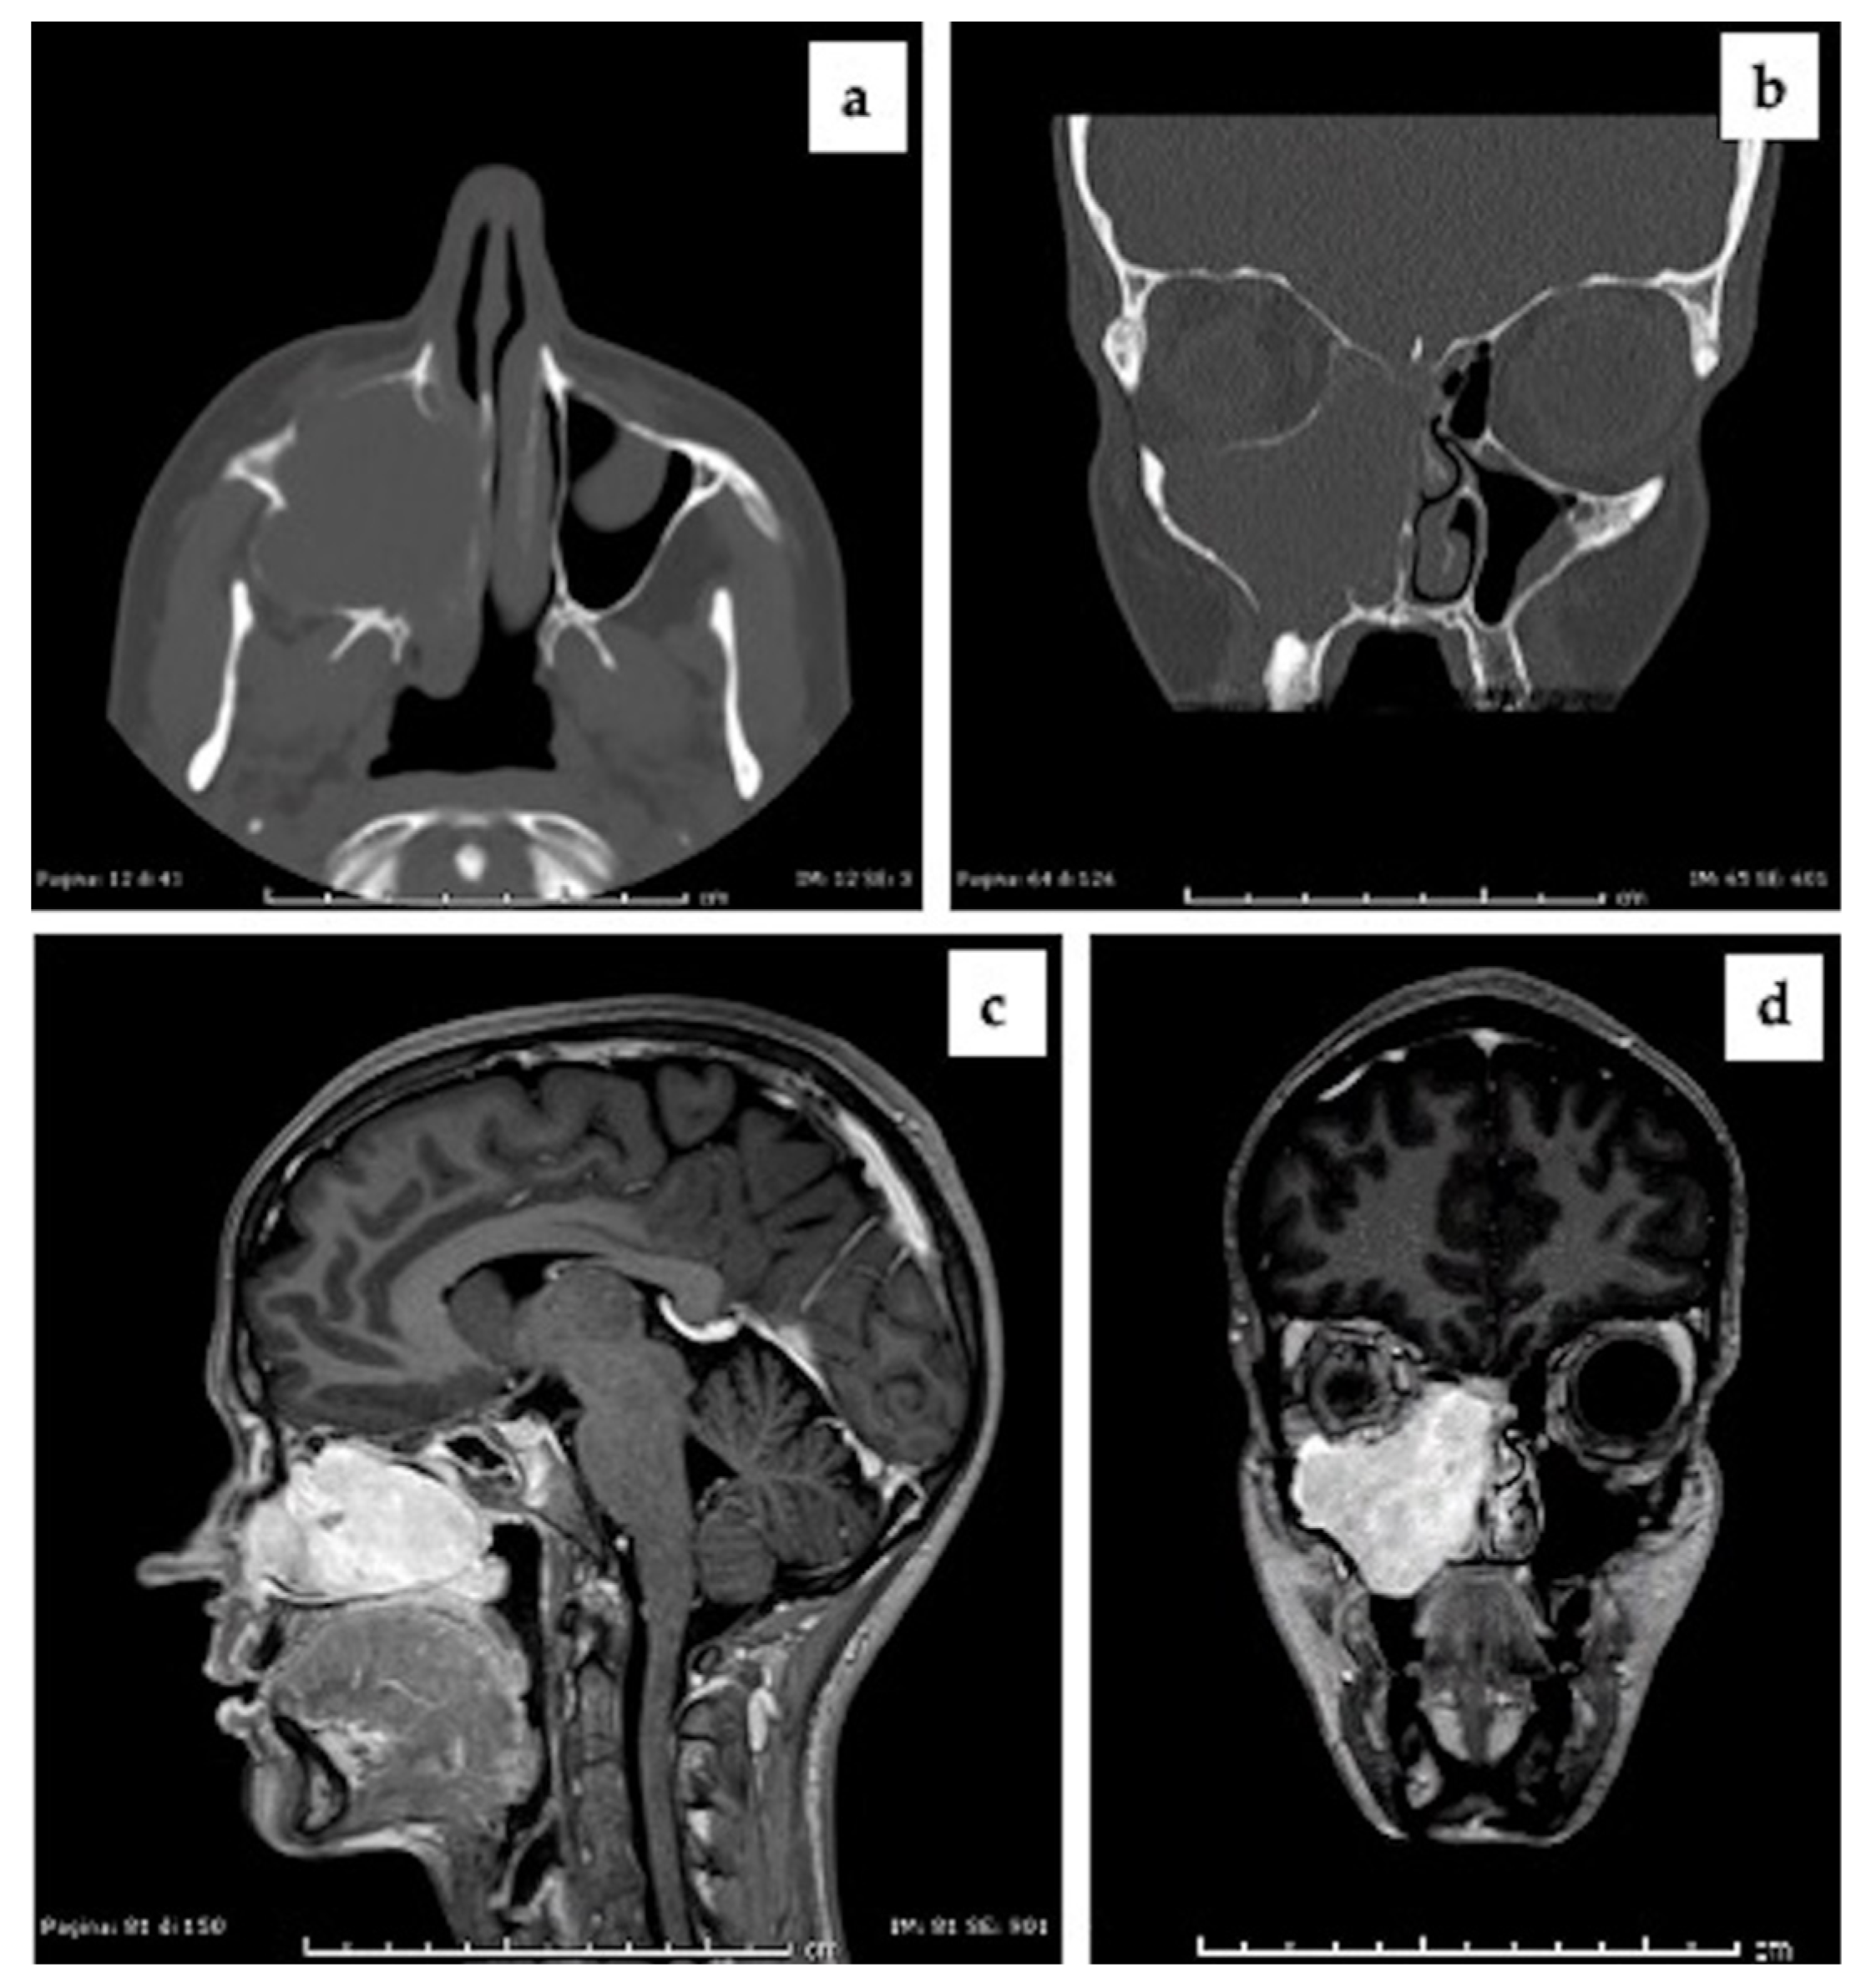

2.1. Clinical Presentation and Preoperative Imaging